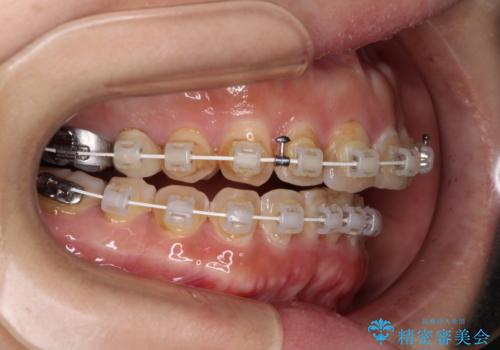

- 審美装置

なるべく早めに治療を終えたいとのことで、補助装置を用いて上顎臼歯を後方に移動させ、同時にワイヤー装置にて整えることとしました。

舌の突出癖が原因で上下の歯に大きなスペースが生じていたため、舌のトレーニングをしっかり行っていただくことで、上顎歯列をスムーズに移動させることができました。